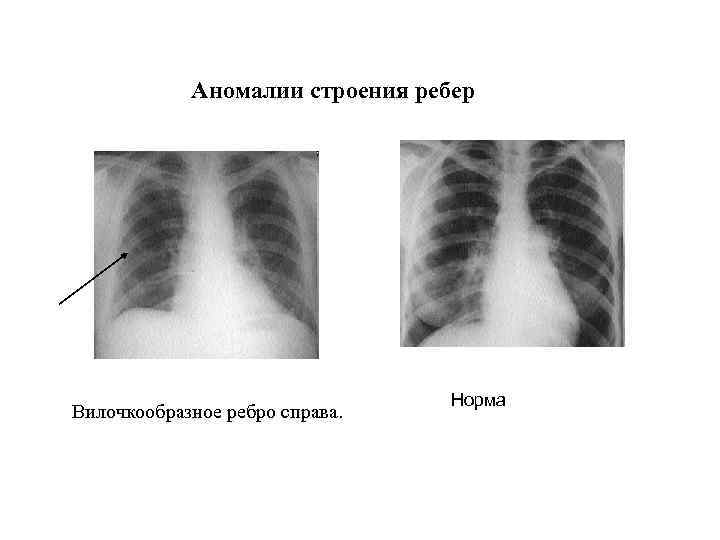

Медицина и диагностика: Аномалии ребер на рентгене